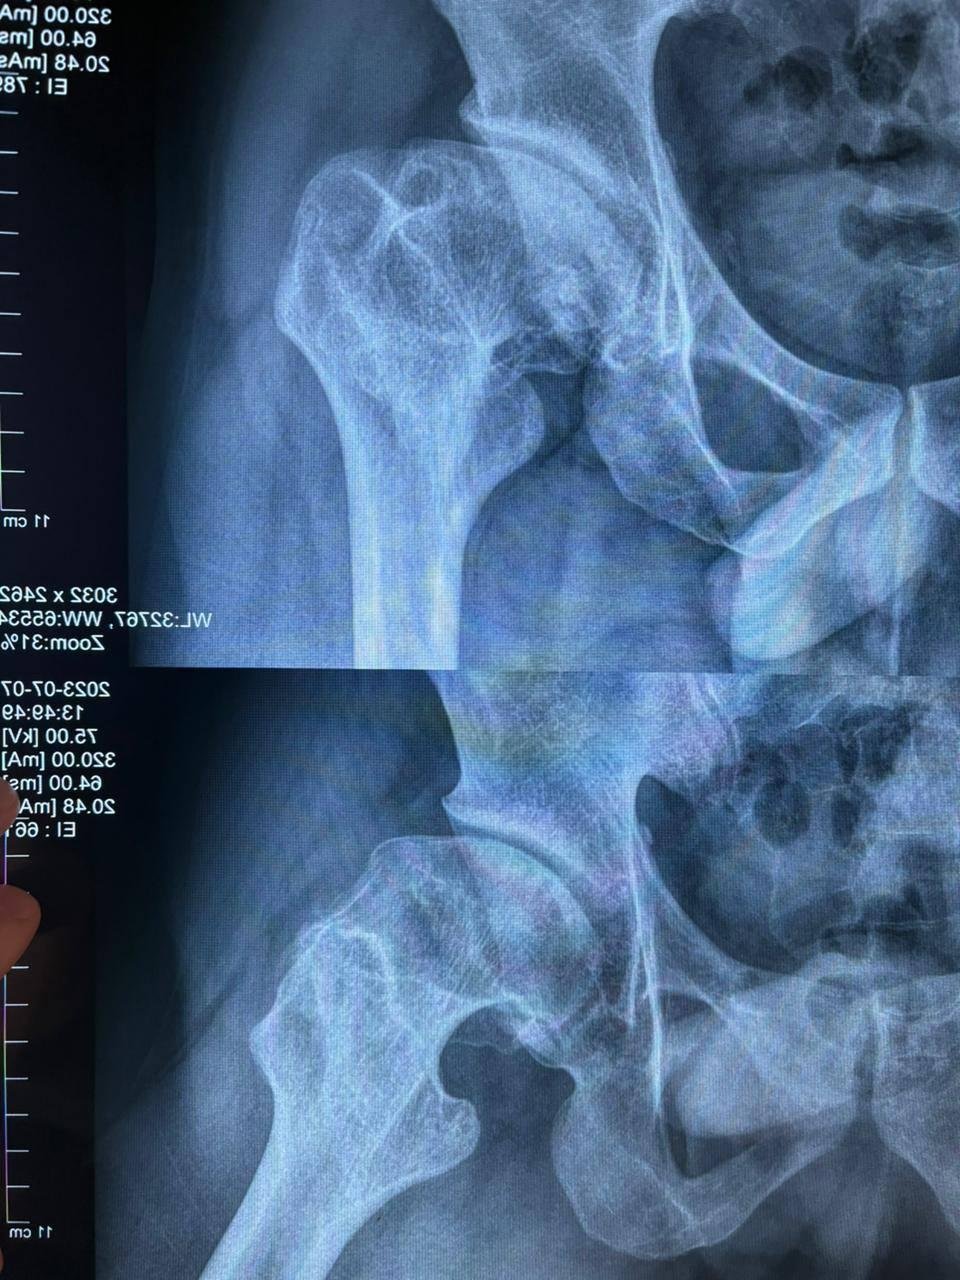

Звучит сложновато, так что вот картинка как выглядит жопа автора (а вы за это еще и заплатили)

Цитата одного из врачей когда он посмотрел снимок

Я вижу серьёзные изменения сустава. Причина, вероятно, в юношеском эпифизеолизе в детстве или в асептическом некрозе. Сейчас уже выраженные вторичные изменения, если сустав болит, то надо думать об эндопротезировании.

Что именно у меня было, я не знаю. Как мне сказала бабушка, в 5–6 лет, когда я уже хорошо ходил, я начал прихрамывать, а потом вообще перестал наступать на ногу. Меня отвели в больницу, полечили. Врач настоятельно рекомендовал не забрасывать это дело и продолжать лечение, но так как я снова начал ходить и жалоб не было, на это в итоге забили.

Врачу в больнице я продолжил ныть, но, как я понял, сустав уже тогда выглядел не очень, и мне написали в заключении: коксартроз тазобедренного сустава 2–3 степени (я думаю была первая, хотя хз). Когда я принёс документы в военкомат, меня буквально послали нахуй, так как до этого я уже года полтора сливался с призыва и косил.